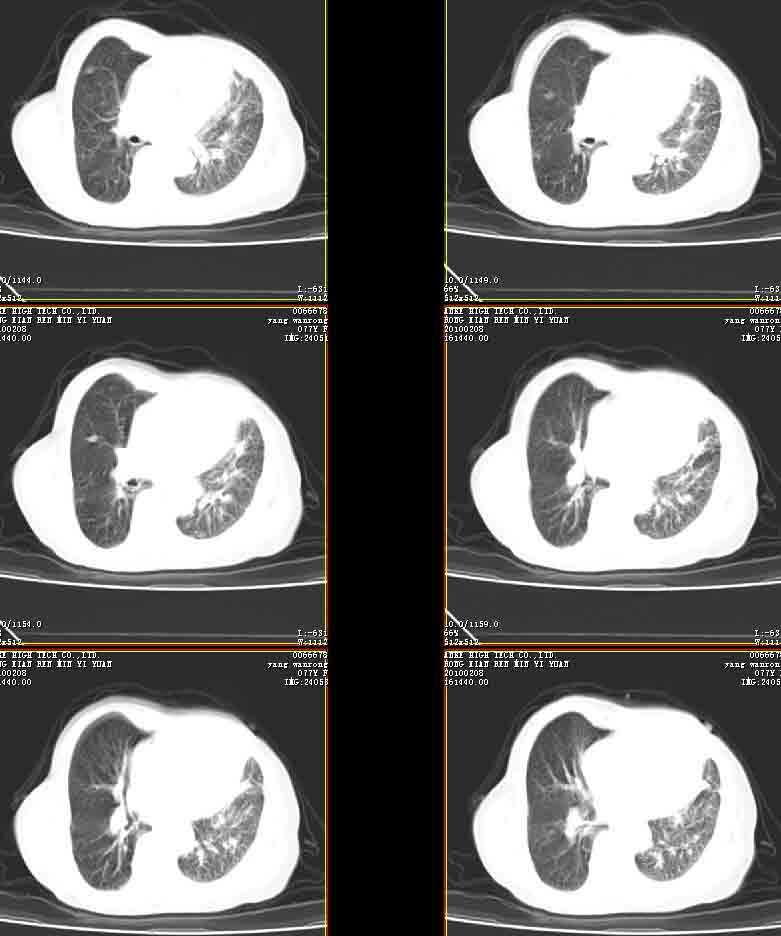

女77岁因左侧胸痛伴咳嗽入院;提示:病灶平扫45hu,强化145hu补充:双肺内未闻及干湿罗音

我的诊断意见:左肺上叶前段肺癌伴节段性不张。

在不张的肺内见到不规则的软组织,而且强化是不均匀的(该点可能是我的图像作得不好的原因)。

右肺近胸膜下区散在结节,性质?

请教左侧肺含气不良用什么解释更好?

左上肺前段可见分叶团块影,强化明显,周围见带状不张影,右肺结节,左肺沿肺纹模糊片状影,考虑左上肺占位,肺癌可能性大。

考虑左肺上叶前段肺癌伴节段性不张、肺内转移,建议薄层扫描。